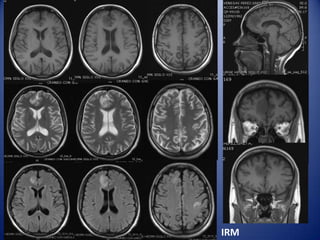

MRI white-matter lesions in NPSLE

•

↑ signal in Τ2 / FLAIR

• Localized in subcortical and periventricular

white matter and frontal-parietal lobe (70–80%)

• Prevalence 50–60% of all patients with NPSLE

…but 18–40% of non-NPSLE

…no correlation with a particular NP syndrome

• Cerebral atrophy, number and size of WML and cerebral infarcts

correlate with severity of cognitive dysfunction

In young SLE patients new MRI WMLs (especially if ≥5, ≥6-8mm, and

bilateral may suggest active NPSLE

IRM

MRI Diagnosis

Radiology: Infarcts (embolus), cortical,

in two different territories, restricted

diffusion, low ADC.

Neurology: Opportunistic infection

(toxoplasmosis) vs. brain abscess

MRI in NP SLE

Multiple white matter lesions.

Cerebral infarction.

Cerebral hemorrhage.

Venous sinus thrombosis.

Atrophic changes.

Spinal cord disease.

Saggital T1 image: Clot in the Stright sinus